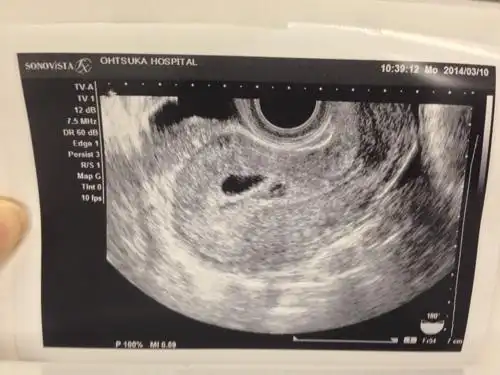

[试管婴儿]刚刚突然排出来这个之后,肚子就

胎囊是什么样子

怀孕5周零5天了,这是胎囊吗?